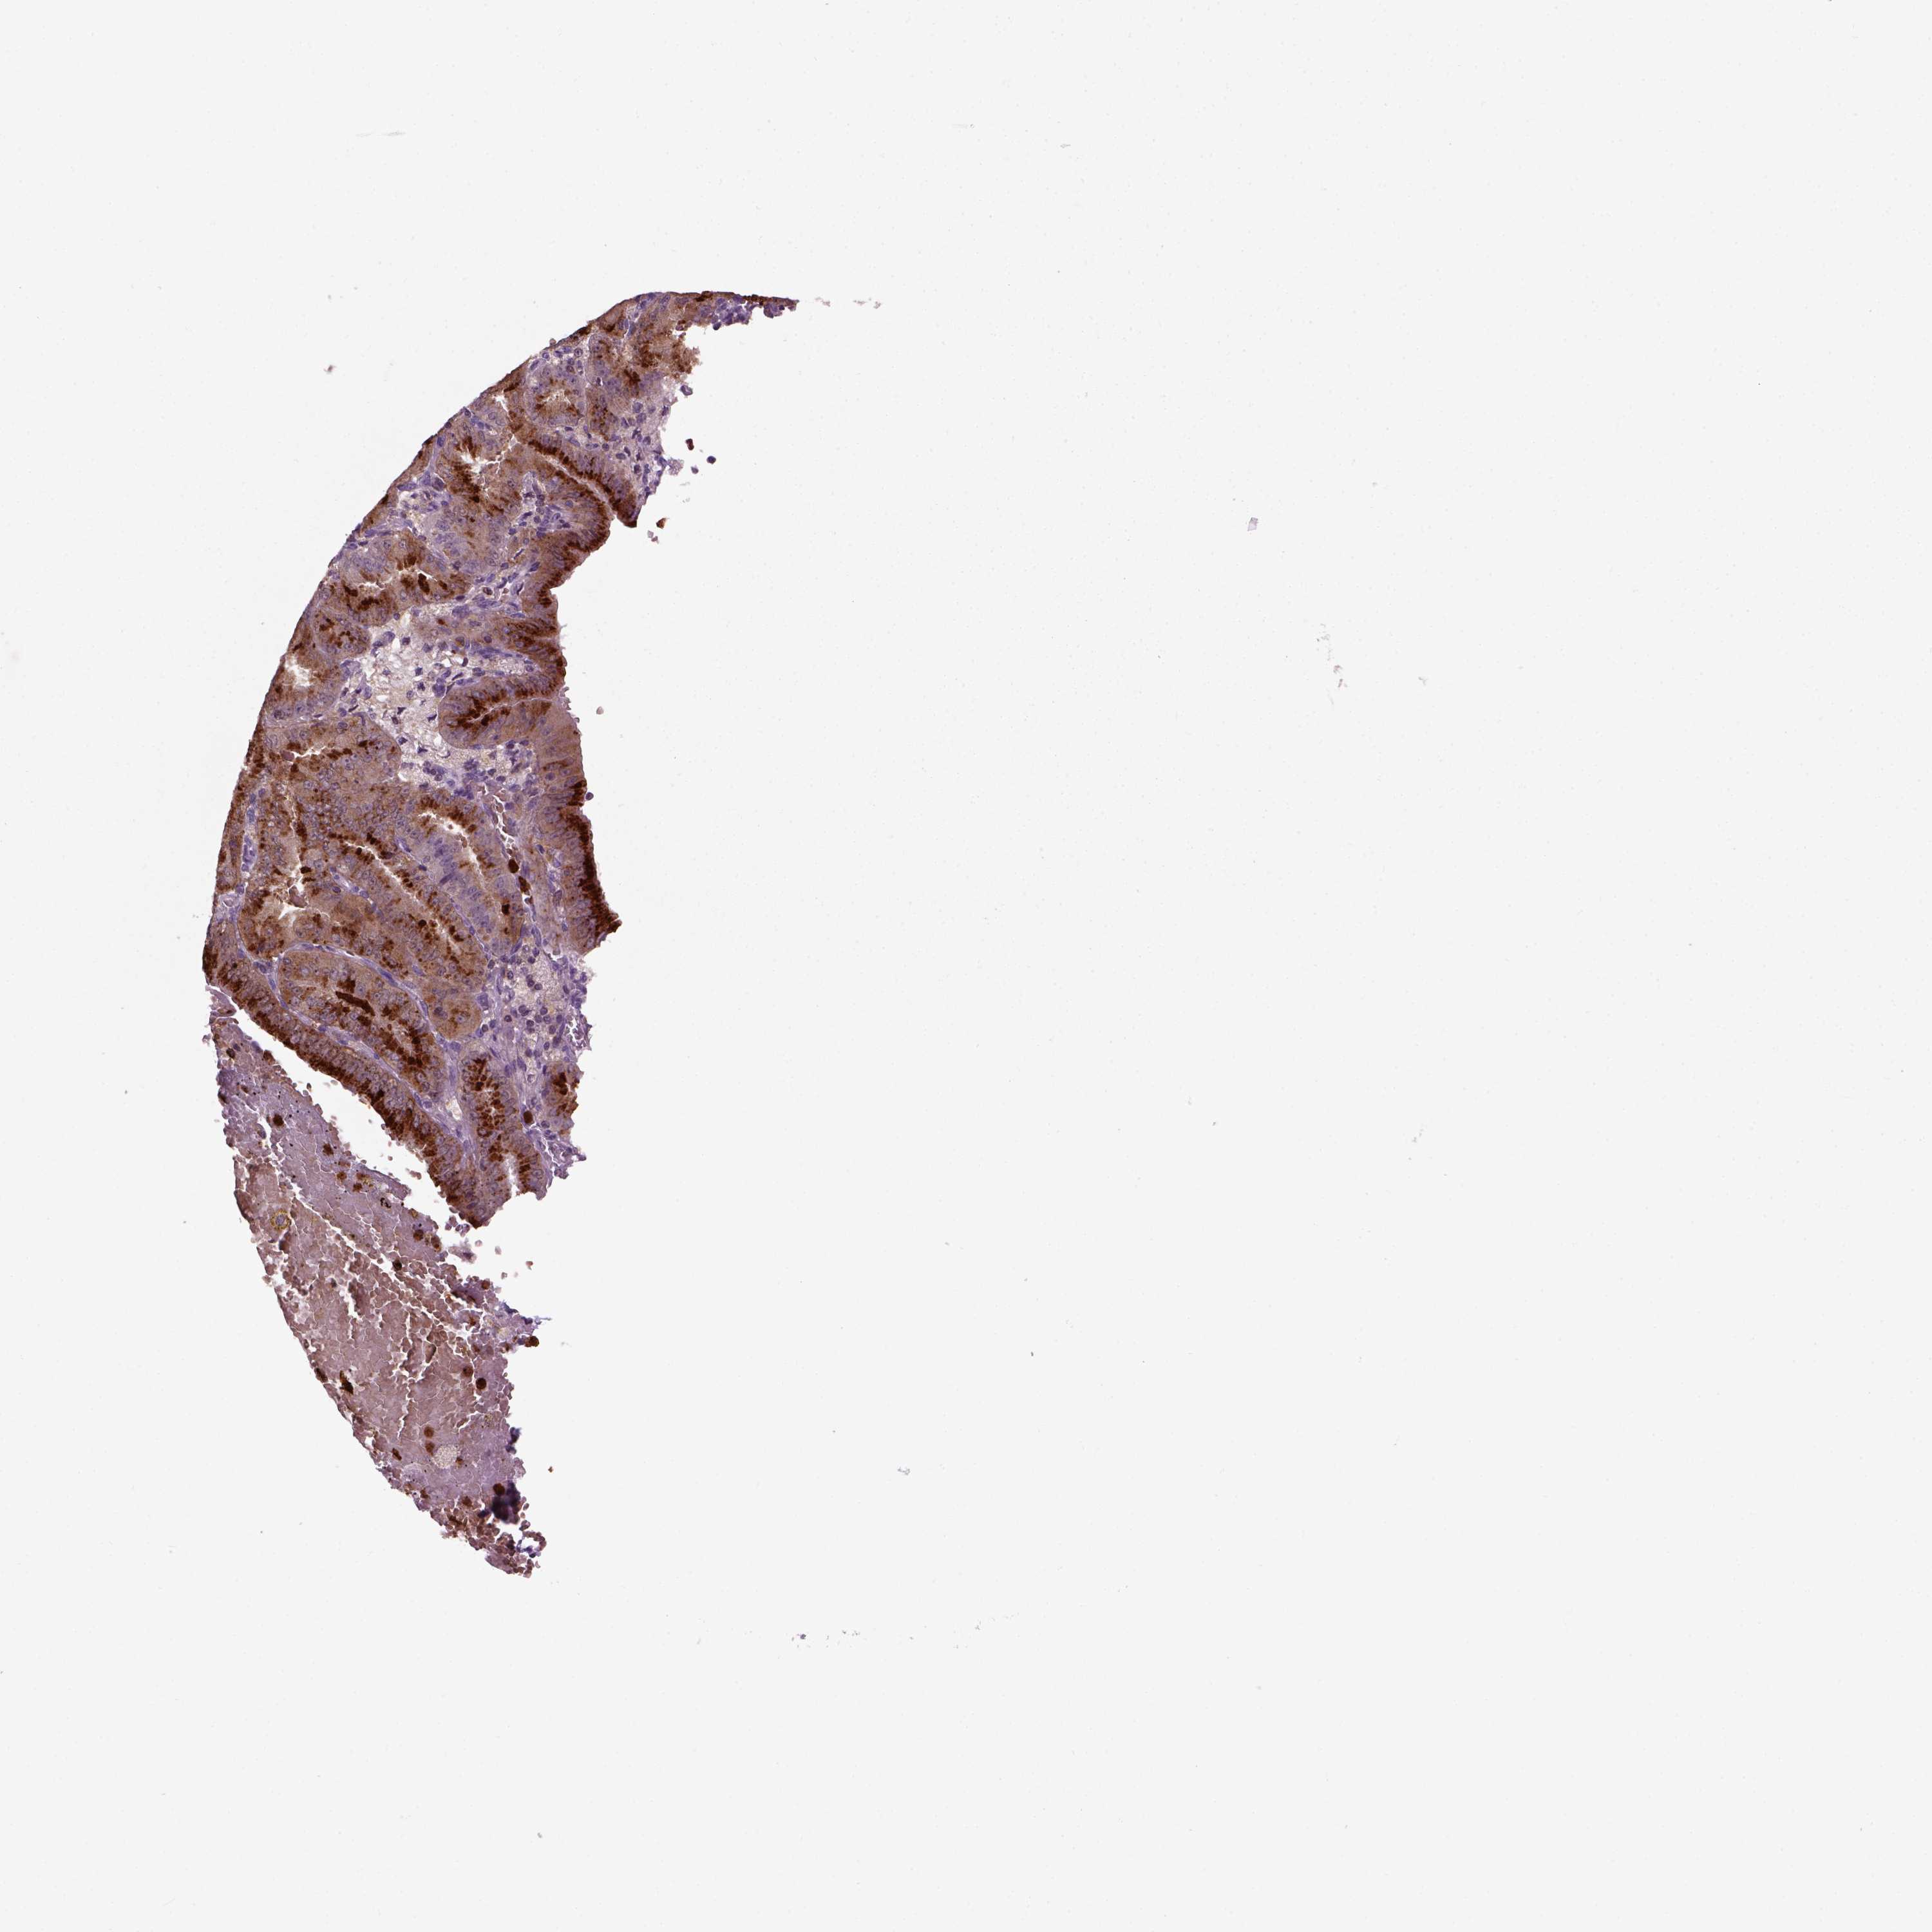

ENDOMETRIAL CANCER - Protein expressioni

A mouse-over function shows sample information and annotation data. Click on an image to view it in a full screen mode. Samples can be filtered based on level of antibody staining by selecting one or several of the following categories: high, medium, low and not detected. The assay and annotation is described here.

Note that samples used for immunohistochemistry by the Human Protein Atlas do not correspond to samples in the TCGA dataset.

Antibody stainingi

Antibody staining in the annotated cell types in the current human tissue is reported as not detected, low, medium, or high, based on conventional immunohistochemistry profiling in selected tissues. This score is based on the combination of the staining intensity and fraction of stained cells.

Each image is clickable and will lead to virtual microscopy that enables deeper exploration of all samples and also displays staining intensity scores, fraction scores and subcellular localization as well as patient and tissue information for each sample.

Antibody HPA044186

Antibody HPA063605

Staining

High

Medium

Low

Not detected

Intensity

Strong

Moderate

Weak

Negative

Quantity

>75%

75%-25%

<25%

None

Location

Nuclear

Cytoplasmic/membranous

Cytoplasmic/membranous,nuclear

Adenocarcinoma, NOS

Adenocarcinoma, metastatic, NOS